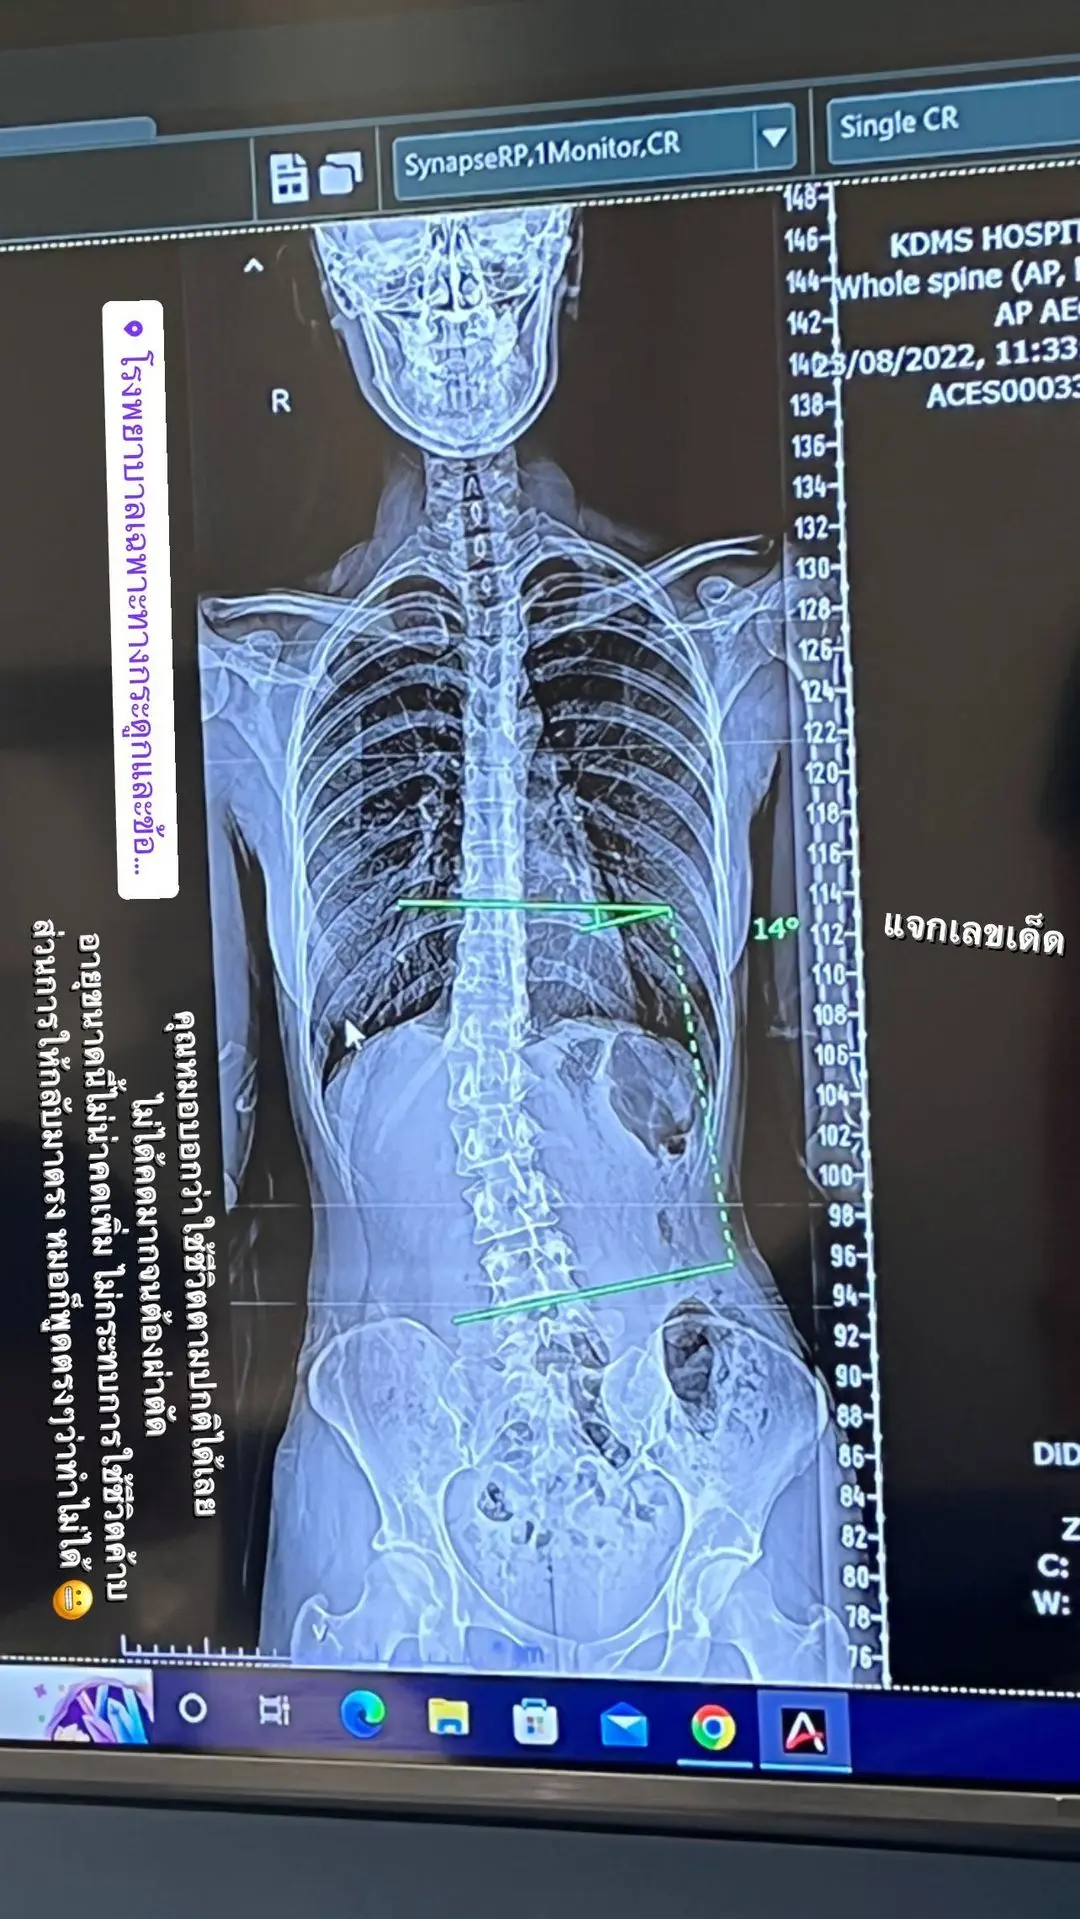

ล่าสุด (23 ส.ค. 65) ส้ม มารี ได้โพสต์ภาพผลการเอกซเรย์ผ่านทางไอจีสตอรี่ @zommarie พร้อมระบุว่า “คุณหมอบอกว่าใช้ชีวิตตามปกติได้เลย ไม่ได้คดมากจนต้องผ่าตัด อายุขนาดนี้ไม่น่าคดเพิ่ม ไม่กระทบการใช้ชีวิต ส่วนการให้กลับมาตรง หมอก็พูดตรง ๆ ว่าทำไม่ได้”

นอกจากนี้ ส้ม มารี ยังได้โพสต์ข้อความขอบคุณแฟน ๆ ทุกคนที่เป็นห่วง เจ้าตัวเผยว่า คนทัก DM แตกมาก ๆ ดีใจที่มีคนรักและเป็นห่วงเยอะขนาดนี้ จริง ๆ รู้เรื่องหลังตัวเองคดมานานมาก ๆ แล้ว เคยเอกซเรย์เมื่อหลายปีก่อน ซึ่งตอนนั้นคุณหมอคนก่อนก็บอกเหมือนกันว่าไม่ได้อันตราย ไม่ได้คดเยอะ ใช้ชีวิตต่อไปได้ปกติ มองโลกในแง่ดี คือเวลาถ่ายรูป ถ้ารู้มุมบิดตัว ฉันจะเอวเอสอยู่ข้างหนึ่งที่มากกว่าอีกข้าง